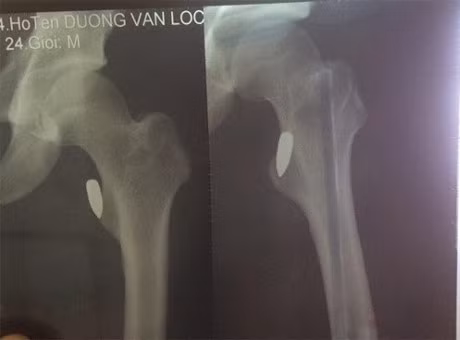

| Hình chụp vết thương của nạn nhân. |

Trước đó, trưa 26-9, Dương Văn Lộc (24 tuổi, vận động viên Pencak silat tỉnh Vĩnh Phúc) sau buổi tập cùng với đội tuyển đã cùng người bạn tên Thiện lấy xe máy đi uống nước. Vừa đi qua ngã tư chợ Tổng (TP. Vĩnh Yên) thì Lộc nghe thấy tiếng nổ, sau đó đùi anh đau buốt và chảy máu nhiều nên phải đưa đi viện cấp cứu.

Bác sĩ chẩn đoán trong đùi anh Lộc có viên đạn. Vì vết thương khá phức tạp nên sau khi sơ cứu, anh Lộc được chuyển xuống Bệnh viện Việt Đức (Hà Nội). Tổn thương do đạn gây ra khá phức tạp nên các bác sĩ vẫn chưa thể gắp đầu đạn ra ngoài.